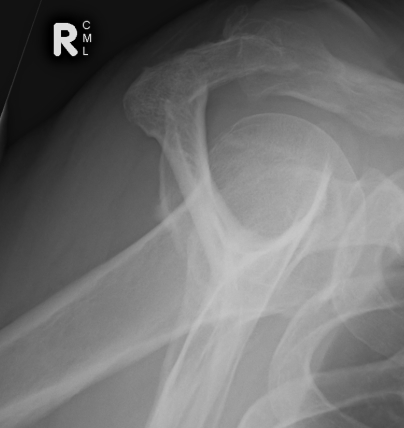

X-ray

| AP | Supraspinatus outlet view | Axillary lateral |

|---|---|---|

|

Sclerosis greater tuberosity / acromion Lateral Acromion spur |

Acromial morphology | Os acromiale |